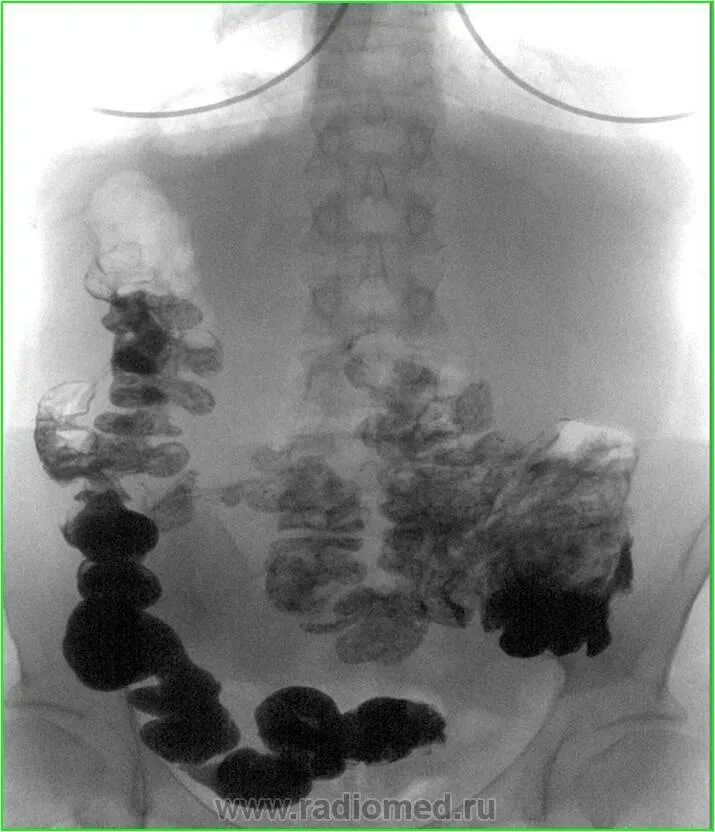

Ирригоскопия с двойным контрастированием